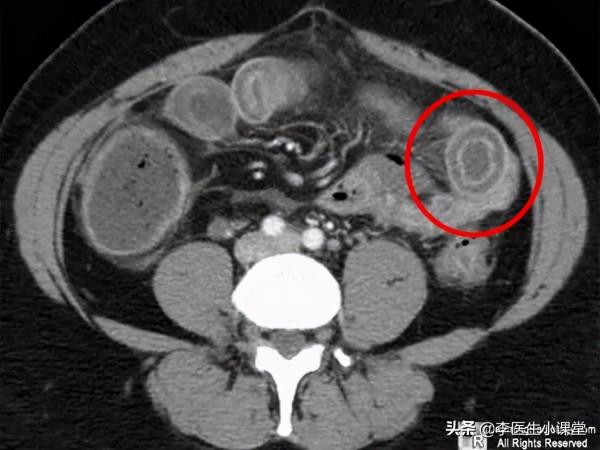

3.藉助CT或者磁共振腸道顯像能夠知道到病變的位置、範圍、腸道是否有狹窄以及一些腸外併發症,可以作為小腸CD的常規檢查手段;

克羅恩病活動期在CTE影像學上的表現有比較明顯的特點—腸壁增厚+分層改變、腸粘膜、粘膜內層與漿膜外層密度都增加,看上去就像一個靶子,醫學上將此稱為“靶徵”;當腸繫膜的血管增多扭曲並且發生擴張,影象上看起來形似木梳,也就是所稱的“木梳徵”;